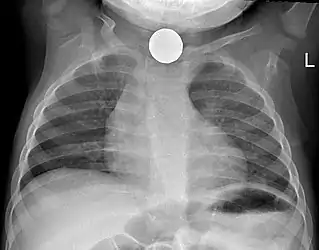

Prior to undertaking endoscopy, attempts should be made to locate the foreign body with x-rays or other non-invasive techniques.[1] For radio-opaque objects, x-rays of the neck, chest and abdomen can be used to locate the foreign body and assist endoscopy.[9] Alternative approaches, including the use of metal detectors, have also been described.[10]

X-rays are also useful for identifying the type of foreign body ingested and complications of foreign body ingestion, including mediastinitis and perforation of the esophagus.[1]